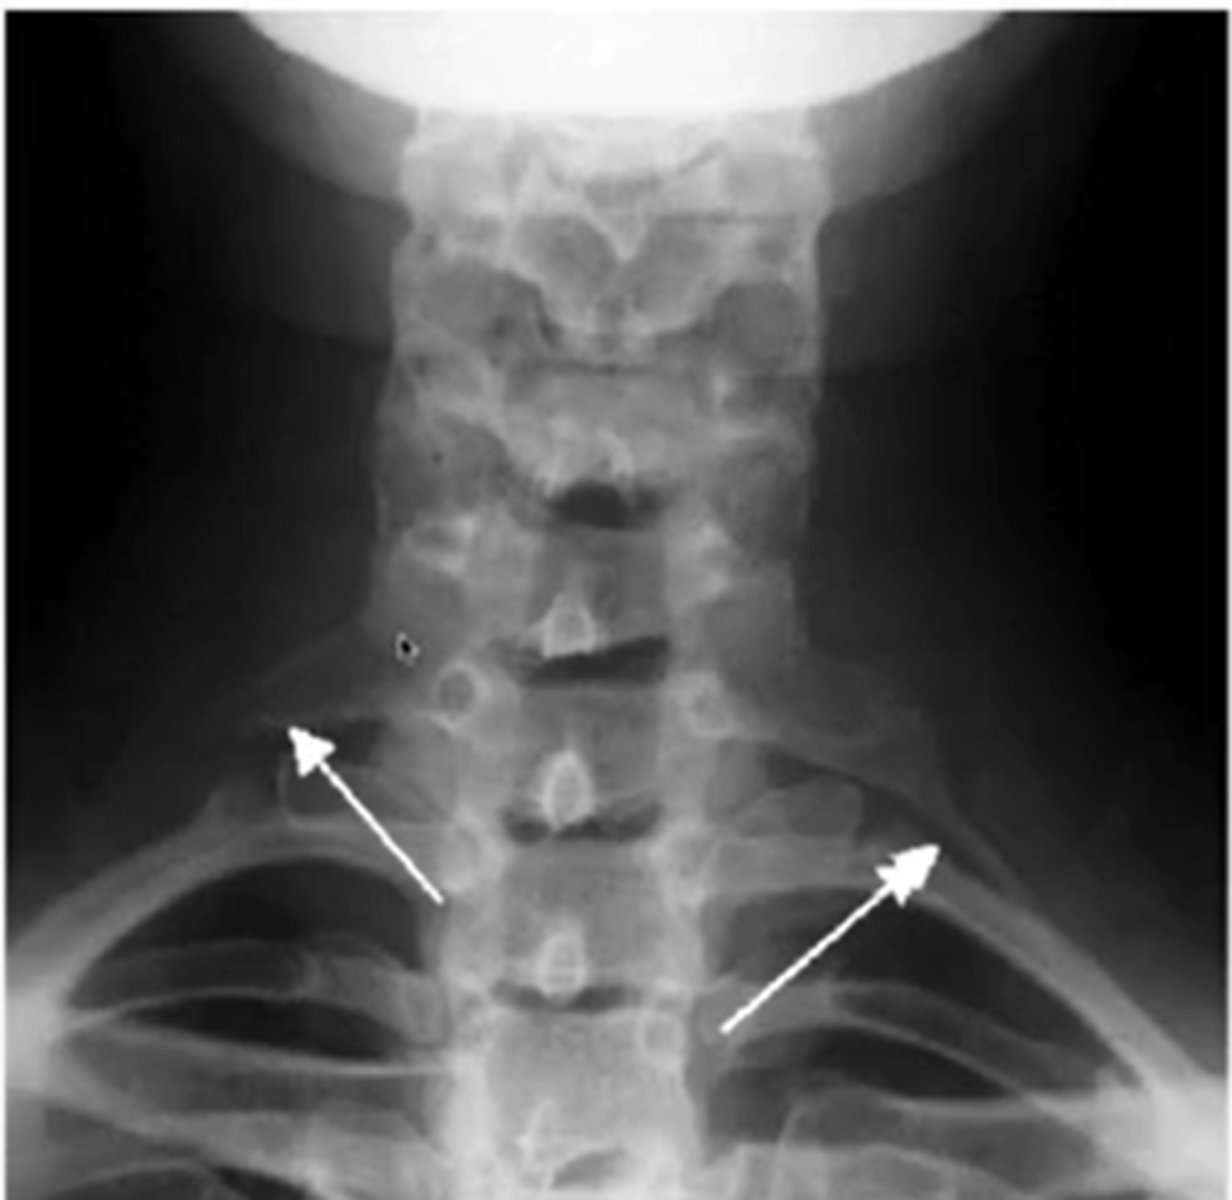

at what angle is the ap cs taken?

15-20 deg

what does a normal AP cs look like

AP

what are you looking for during AP view of CS